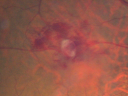

Macroaneurysm FP1068 viewsMacroaneurysm with Subretinal Hemorrhage and ME in OS of an Elderly Female

|